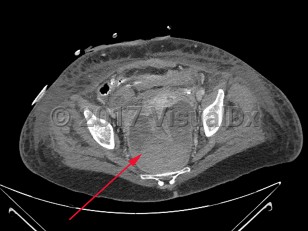

Imaging Studies image of Perirectal abscess - imageId=7915658. Click to open in gallery.  caption: '<span>Axial CT image of a  large perirectal abscess with hemorrhage in a patient recently  postoperative with rectal perforation.</span>'

Axial CT image of a large perirectal abscess with hemorrhage in a patient recently postoperative with rectal perforation.